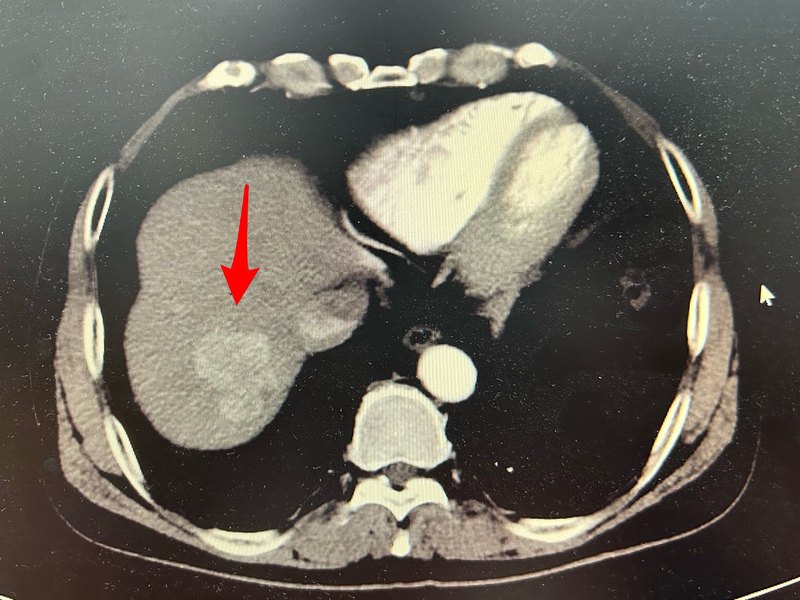

患者男性,45歲,2022年1月,發(fā)現(xiàn)右肝巨大腫瘤并肝內(nèi)子灶,肝門部淋巴結(jié)可疑轉(zhuǎn)移,外科評(píng)估手術(shù)難度風(fēng)險(xiǎn)大,暫不建議外科手術(shù),遂先行介入治療。下圖是術(shù)前CT。造影見(jiàn)腫瘤巨大但是染色并不明顯,考慮碘油難以滿意沉積,故選擇100-300um載藥微球栓塞治療,右圖是栓塞后再次造影未見(jiàn)腫瘤血管染色。術(shù)后CT腫瘤基本壞死,AFP從673下降到70,我們對(duì)子灶先做根治性消融治療,一月后對(duì)大腫瘤也做了一次微波消融治療,由于腫瘤和腸道粘連,未追求完全消融,患者同時(shí)聯(lián)合靶向及免疫治療,也同時(shí)采取中藥治療。消融后復(fù)查AFP37,腫瘤明顯縮小,外科再次評(píng)估,認(rèn)為有手術(shù)指征,22年5月在寶安中心醫(yī)院肝膽外科行行肝癌切除術(shù),術(shù)后病理提示肝細(xì)胞癌并肝十二指腸韌帶淋巴結(jié)轉(zhuǎn)移。這個(gè)案例我們沒(méi)有采取當(dāng)時(shí)主流HAIC的方案,因?yàn)镠AIC需要多次長(zhǎng)時(shí)間灌注化療藥,對(duì)肝功能及全身的影響較大,而是采取1次微球栓塞、2次微波消融聯(lián)合靶免實(shí)現(xiàn)快速轉(zhuǎn)化,避免多次HAIC引起的肝功能及全身的損傷。術(shù)后患者密切隨診并行TACE治療,2022年11月發(fā)現(xiàn)右肝腫瘤復(fù)發(fā),行TACE加微波消融術(shù),術(shù)后病灶局部完全滅活。右肝復(fù)發(fā)腫瘤消融治療后完全滅活。2023年2月發(fā)現(xiàn)胸部轉(zhuǎn)移灶,緊貼升主動(dòng)脈,考慮消融治療風(fēng)險(xiǎn)較大,行粒子植入治療,粒子植入術(shù)后多次復(fù)診,局部腫瘤完全滅活。主動(dòng)脈弓旁腫瘤。粒子準(zhǔn)確釋放在腫瘤內(nèi),主動(dòng)脈無(wú)損傷,多次隨訪局部腫瘤完全滅活。2023年8月肝內(nèi)腫瘤再次復(fù)發(fā),行TACE治療,但無(wú)碘油沉積,遂行微波消融治療。術(shù)后病灶完全滅活。右肝膈頂部復(fù)發(fā)腫瘤消融后,多次隨診腫瘤無(wú)復(fù)發(fā),術(shù)后無(wú)氣胸及胸腔積液。2023年10月發(fā)現(xiàn)腹膜后淋巴結(jié)及肝門區(qū)腫瘤復(fù)發(fā),行TACE治療,效果不理想。腹膜后及第一肝門處腫瘤復(fù)發(fā),患者出現(xiàn)疼痛及納差消瘦。行介入治療但效果不滿意。2023年10月,2023年12月,2024年1月行粒子植入治療,兩個(gè)位置穿刺難度均非常大,小心翼翼,克服各種困難,終于把粒子釋放在滿意的位置。腹膜后腫瘤分別采取前入路及后入路兩次釋放粒子才達(dá)到滿意效果,肝門腫瘤緊靠小腸,采取側(cè)方入路進(jìn)針釋放粒子,最后兩個(gè)部分粒子均比較準(zhǔn)確釋放,沒(méi)有發(fā)生棘手并發(fā)癥。術(shù)后多次隨診,腫瘤均控制良好,但是患者身體逐漸衰弱,納差消瘦乏力。2024年6月開(kāi)始患者出現(xiàn)胸腔反復(fù)積液,肺部感染,后來(lái)出現(xiàn)咯膽汁,右肝膿腫,多家醫(yī)院保守治療效果不佳,2024年8月行右肝膿腫置管引流?;颊叱霈F(xiàn)膽汁支氣管瘺行置管引流減輕癥狀。2024年9月行ERCP植入膽道支架減輕膽汁支氣管瘺。2024年11月,患者因全身衰竭去世。點(diǎn)評(píng):患者2022年1月發(fā)病,2024年11月去世,總生存34個(gè)月,對(duì)于一個(gè)IIIB期肝癌患者而言,總體生存期算基本滿意。這個(gè)患者累計(jì)住院二十余次,雖然每次治療都采用相對(duì)便宜的器械,但是醫(yī)療總費(fèi)用其實(shí)還是比較高昂?;颊吆竺姘肽晟眢w虛弱,且反復(fù)胸腔積液,肺部感染及支氣管膽汁瘺導(dǎo)致生活質(zhì)量較差,這是有點(diǎn)令人遺憾的地方。這個(gè)患者不但采取了手術(shù)治療,還做了多次介入治療,四次粒子植入,四次微波消融治療,也聯(lián)合了靶向和免疫治療,整個(gè)治療過(guò)程也有中醫(yī)治療保駕護(hù)航,是一個(gè)綜合了各種手段治療的案例。一個(gè)醫(yī)生即使技術(shù)手段達(dá)到極高的水平,就算每次手術(shù)都做到盡善盡美,依然無(wú)法讓每個(gè)癌癥患者都一直長(zhǎng)期生存,總會(huì)面臨我們的技術(shù)無(wú)能為力的一天,作為患者更加要能接受這個(gè)結(jié)局,根據(jù)自己的實(shí)際情況選擇自己能接受的治療方案,盡量避免最后階段的無(wú)效醫(yī)療。